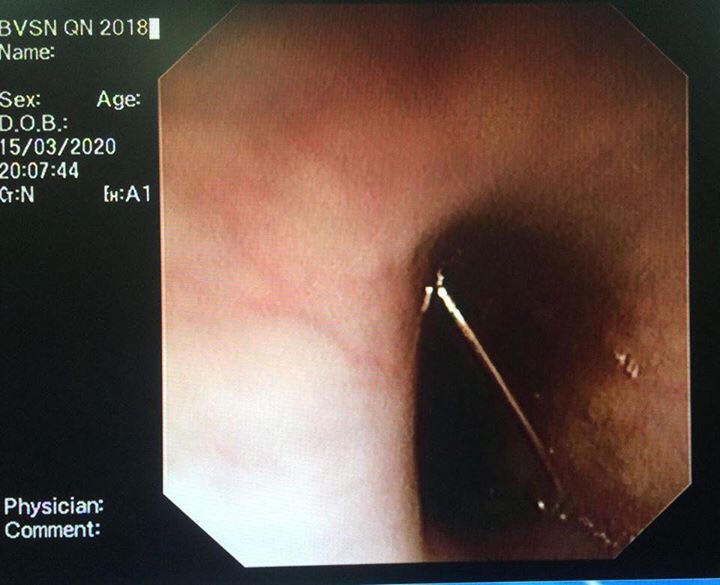

Qua nội soi thực quản, các Bác sĩ quan sát thấy chiếc kim băng trong thực quản của trẻ, xác định được nguyên nhân, kíp phẫu thuật tiến hành dùng kìm đẩy đầu nhọn của kim thoát khỏi thành thực quản, sau đó kẹp lấy đầu nhọn của dị vật rồi kéo ra ngoài cho trẻ.

Bác sĩ Phạm Đăng Hùng cho biết: trường hợp của né N.(04 tuổi) thật may mắn khi kim loại nhỏ, bác sĩ đẩy đầu nhọn ra khỏi thành thực quản, sau đó túm lấy cái đầu nhọn ấy để nó không gây tổn thương thêm cho thực quản. Tránh cho bé một ca phẫu thuật nguy hiểm.